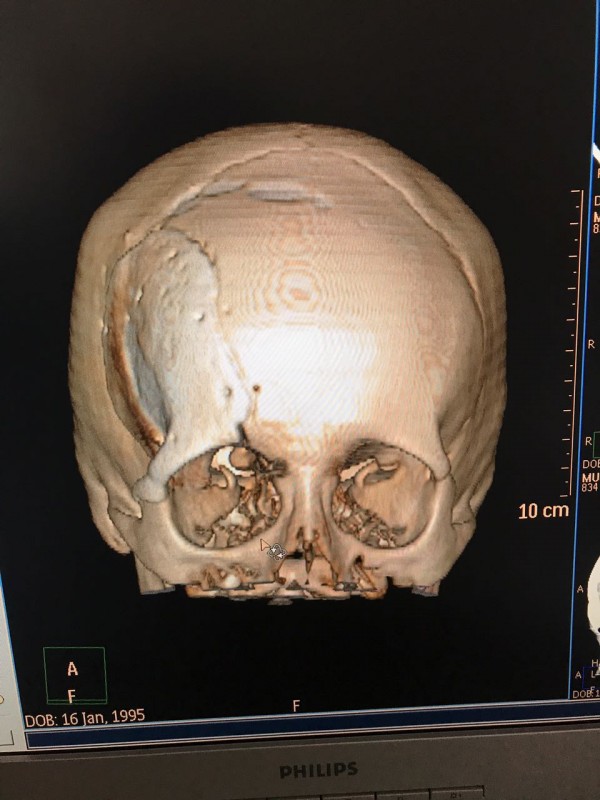

Как рассказал врач-нейрохирург городской клинической больницы № 7 Алматы Константин Ли, предварительный диагноз пациента - "фиброзная дисплазия лобной кости справа", то есть опухолевое поражение костей черепа. По его словам, сложность и уникальность операции в том, что опухоль плотно соприкасалась со зрительным нервом.

"Компьютерная томография показала, что костная опухоль поражала лобную кость и "крышу" орбиты глаза, которая, в свою очередь, сдавливала глазное яблоко. Чтобы убрать опухоль, потребовалось немало времени. Наша задача была сохранить глазное яблоко, зрительный нерв и сосуды. Если неправильно провести операцию и неправильно закрыть дефект, то в последующем это может привести к эстетической неполноте и асимметрии лица. Уникальность еще и в том, что в операции применялась 3D-стереолитография, которая делается только в Алматы", - рассказал он.

Снимок черепа. Опухоль с левой стороны. Фото предоставлено Константином Ли

Снимок сделан до операции. Фото предоставлено Константином Ли